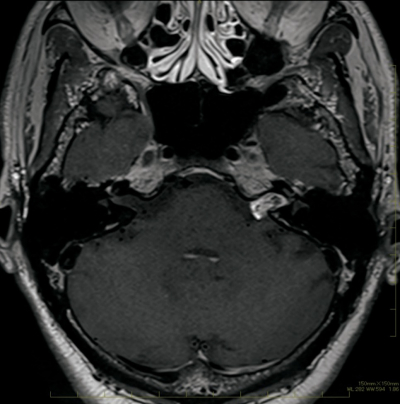

40歳の女性。頭部MRIの異常所見を指摘され来院した。1か月前から時折前頭部の鈍い痛みを自覚している。1週間前に職場同僚がくも膜下出血で入院したため、心配になり自宅近くの医療機関を受診し、頭部MRIで異常を指摘されたため紹介受診した。

身長 162 cm、体重 45 kg。体温 36.2 ℃。脈拍 76/分、整。血圧 124/78 mmHg。身体診察に明らかな異常を認めない。頭部造影MRIを別に示す。